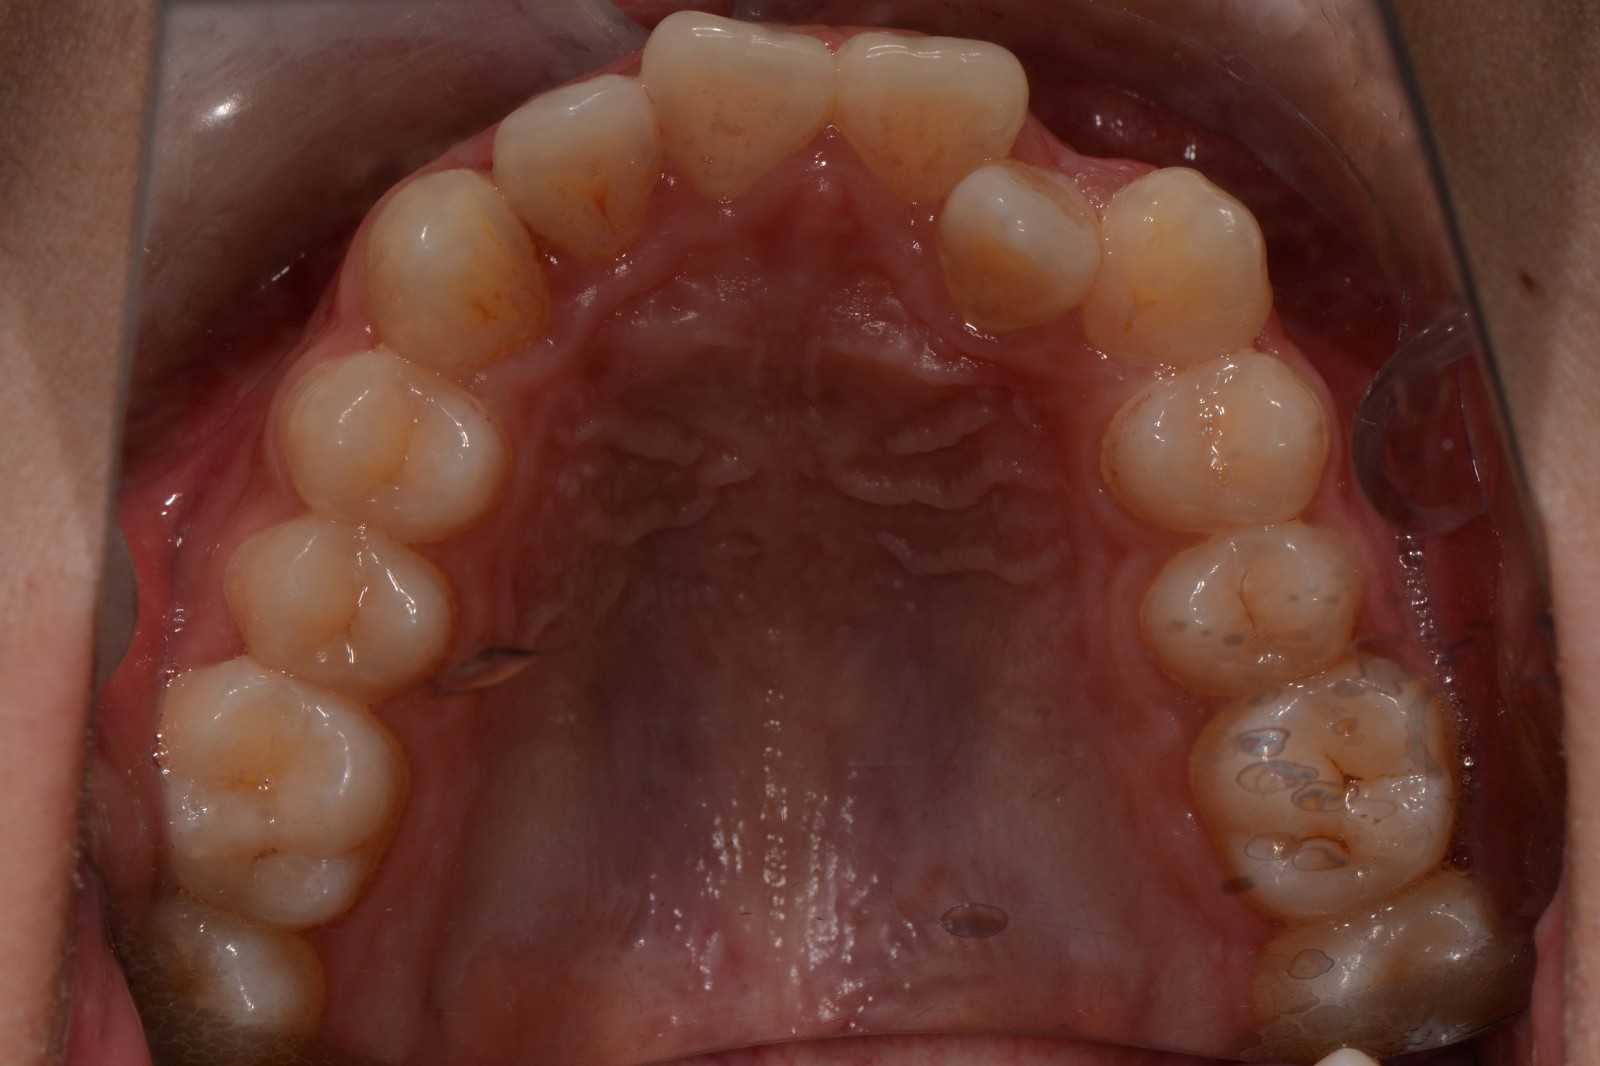

检查:拍摄口内面像照片,拍摄全景片侧位片,口扫,上下颌I-II度拥挤,中线不齐,局部反合,磨牙基本中性关系,上下前牙比较直立。

矫治前: